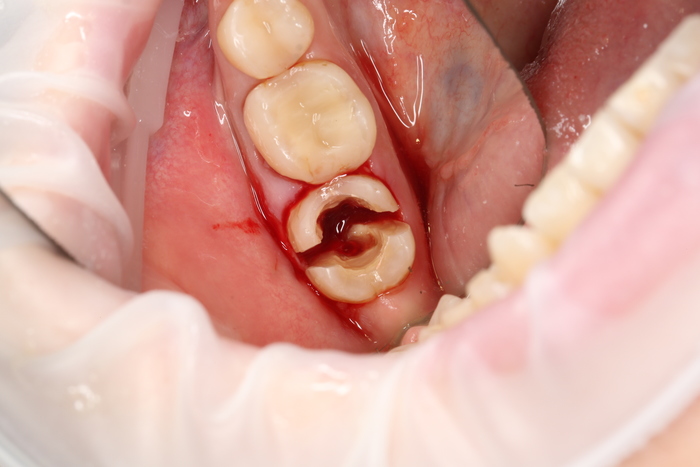

После снятия коронки:

Выкрутили абатмент:

Установлена заглушка, которая закрывает шахту имплантата.